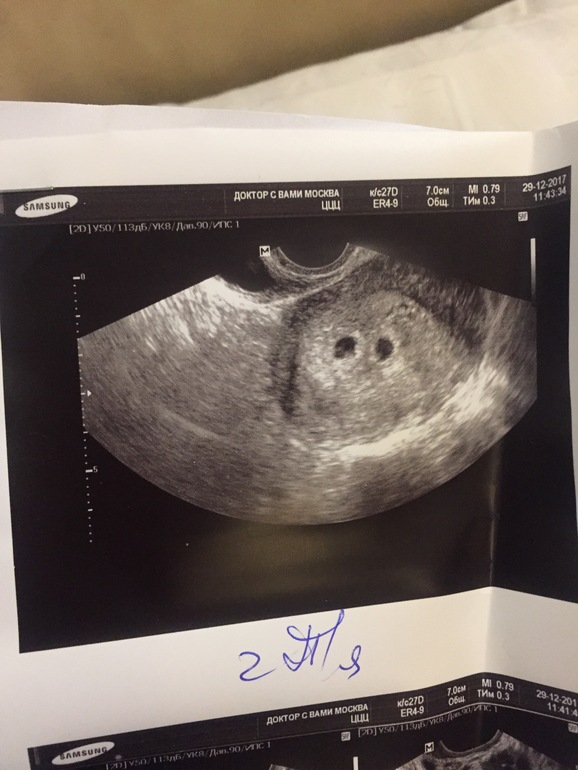

Вопросы про УЗИ, обследования и анализы: что, где, как, когда?Девочки, с мужем ждём третьего малыша) срок сейчас, акушерские 4 недели , по УЗИ 2, вот сделала УЗИ, а мне не даёт покоя то , что рядом с пя, я на УЗИ никогда ничего лишнего не видела) т.е. только четко пя, и все) может ли быть это второй пя? Пересмотрела специально все прошлые УЗИ с двумя детками на таком сроке, ничего такого нет)

Они конечно могут и поближе друг к другу быть, но контуры достаточно четкие.

Я на фото вижу только 1 пя, не накручивание себя. Вам узист сказал что двойня?